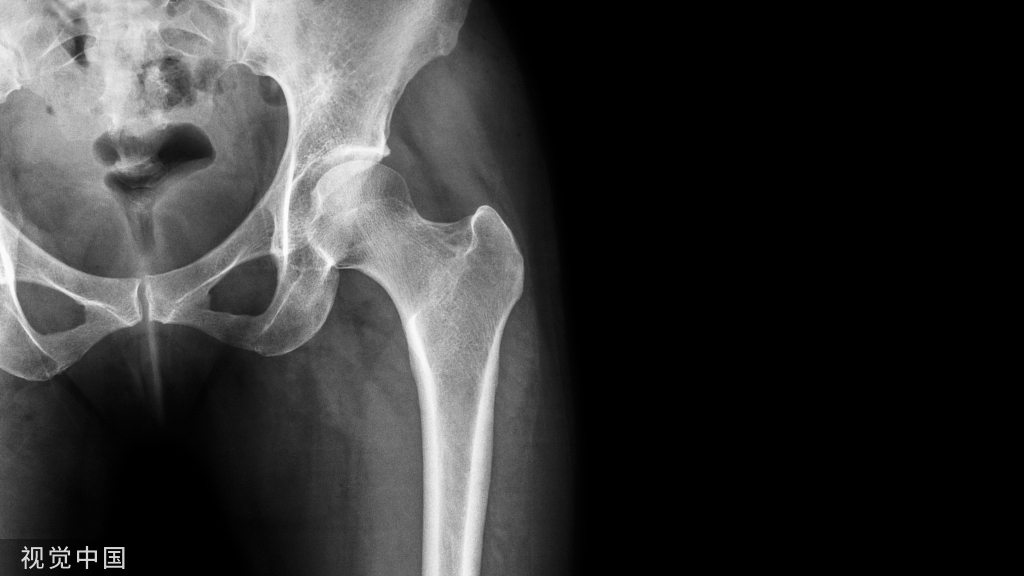

虽然关于孤立性桡骨远端或舟状骨骨折的术后护理有大量的文献,但对于合并损伤的理想恢复时间和固定方法尚不清楚。鉴于目前文献的不足和这种骨折模式所带来的独特挑战,本研究的目的是进一步了解桡骨远端和舟状骨合并骨折的临床和影像学结果。据我们所知,本研究是迄今为止桡骨远端和舟状骨联合骨折n值最大的研究。我们假设这种损伤模式可以根据目前的OA指南有效地管理。

方法:回顾性检索某一级创伤中心数据库15年间(2007-2022年)的成人桡骨远端和舟状骨合并骨折患者。我们对31例患者的损伤机制、骨折处理方法、桡骨远端骨折分类、舟状骨骨折分类、x线片舟状骨愈合时间、运动时间和其他人口统计学数据进行了回顾。对这些患者舟状骨骨折的手术治疗与保守治疗的结果进行了多变量统计分析。